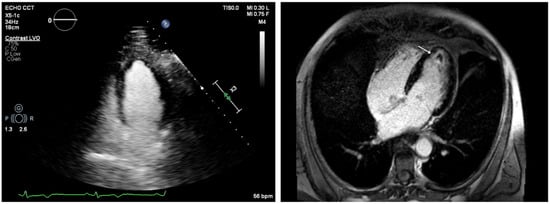

Figure 5.

Patient with Loeffler cardiomyopathy and high suspicion of intracavitary thrombosis due to a transient ischemic attack (TIA). Contrast-enhanced echocardiography does not show intracavitary thrombus in the left ventricle (LV) (left panel; the green line represents the simultaneous electrocardiographic [ECG] recording), whereas CMR reveals a small apical thrombus in the LV apex (white arrow, right panel).